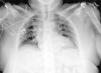

A postoperative chest X-ray was taken at ICU admission (Fig. 1), which revealed a marked right-displacement of the trachea and an increased density area in the mediastinum, which was identified as a hematoma caused by the catheter placement. None of these findings were present in the preoperative chest X-ray (Fig. 2). A computed tomography and thoracic angiography (Fig. 3) were performed and neither active bleeding nor airway compromise was found. The catheter was removed without complications. One week later chest X-ray showed no alterations.